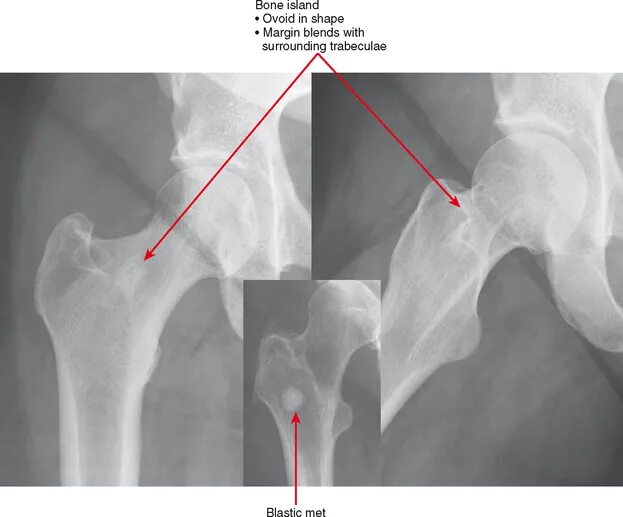

Bone bone shape